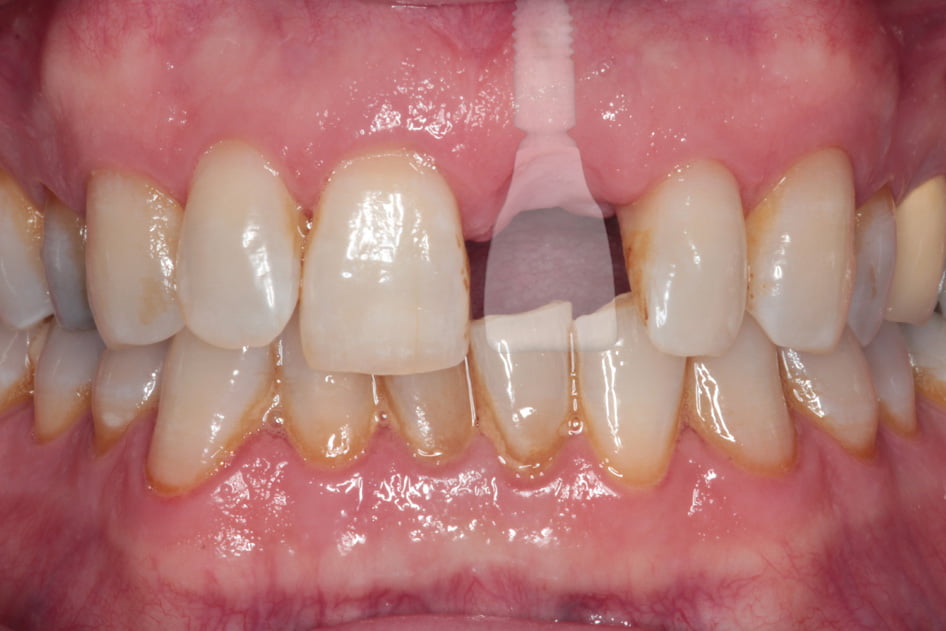

Gallery - Dental Implants

Case 2

Before After